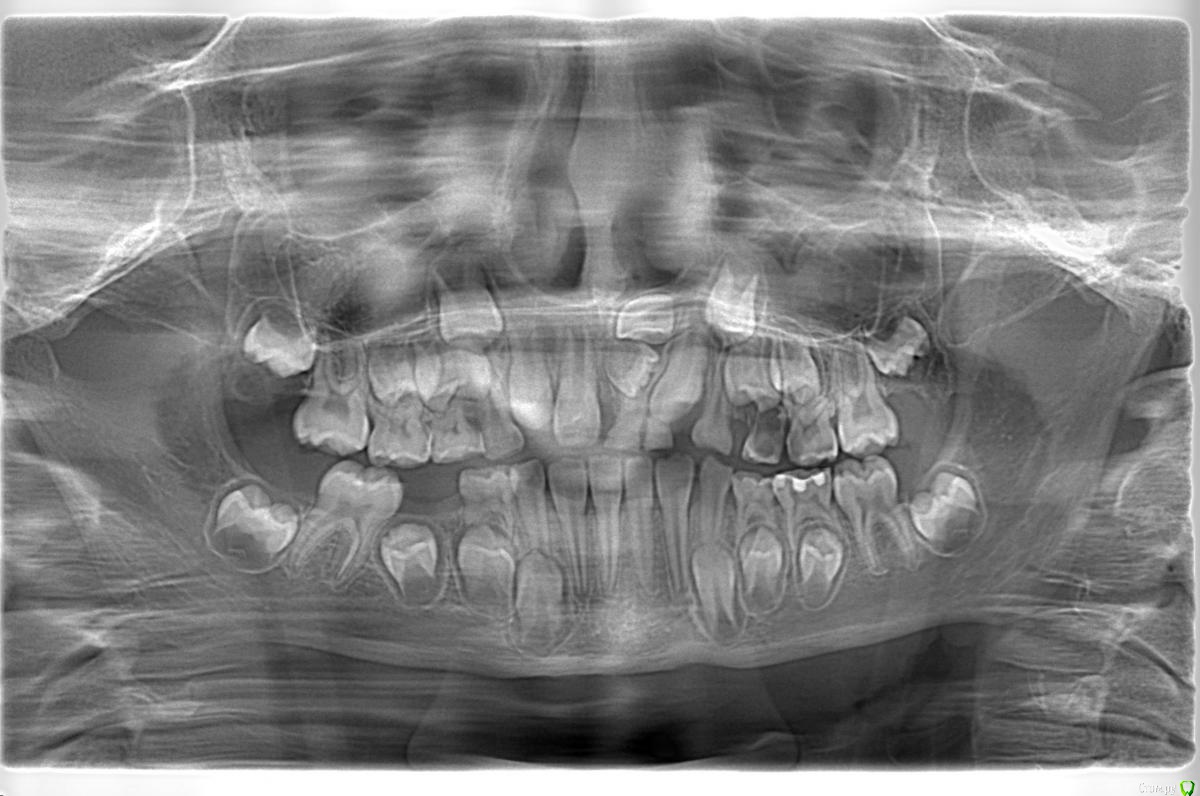

Opdihatop Опубликовано 9 января, 2017 Поделиться Опубликовано 9 января, 2017 Здравствуйте, коллеги! Хотел бы узнать ваше мнение по пациентке. Девочке 7 лет. План лечения в общем мне ясен и понятен. Меня интересует вопрос, когда лучше в данном случае убирать сверхкомплектный премоляр в области 21 зуба, потому что он начал двигать ц.л. вправо. Заранее спасибо! Ссылка на комментарий

Dok22 Опубликовано 11 января, 2017 Поделиться Опубликовано 11 января, 2017 Это не премоляр просто так виден 2-х мерный срез нужно КТ его грамотная интерпретация и хороший хирург.Сверхкомплектный удалять надо он блокирует 21 и 22. Ссылка на комментарий

Давлетшин Опубликовано 12 января, 2017 Поделиться Опубликовано 12 января, 2017 (изменено) С позиции детского амбулаторного хирурга-стоматолога я не трогал бы до окончания формирования корней, а 61, 62 убрал бы. Просто не лез, и не лезу. Да возможно есть есть очень хорошие хирурги с седацией и т.п. пусть они (он, она) решает. Из личного опыта у ребенка сверхкомплектный мешал прорезыванию 21 в семь лет, я все обьяснил сказал:" давайте ждать". Родители понимающе сказали:" давайте", и пошли снова к ортодонту, та в свою очередь отправила к своему "крутому" хирургу. Соответственно сверхкомплектный был удален (сверхкомлектный не прорезался) а у 21 сформирована была только коронка. Через три года, в 10 лет пришли снова, и у меня спрашивают:" где зуб"? Я направил на R-грамму, где увидел что коронка 21 "плавает" в очаге разряжения костной ткани размером 1.5*1.5 см. слизистая была в норме. Об"яснил, рассказал, показал риски для 11 и 22 зуба. и не сформированный 21 был удален. Причем после разреза слизистой и надкостницы с небной стороны сам выпал из полости "кисты". Не знаю где были ошибки. может мне надо было проявить эмоции и внушить что не надо удалять. Не знаю каков был ход операции, задели не задели ростковую зону 21 зуба, нарушили что нибудь не нарушили. Факт что ребенок остался без переднего зуба. Хорошо, мне хватило ума не лезть туда. Может ошибка родителей что не успокоились, и начали панику проявлять. Хирурга в той частной уже не было, наверно импланты крутит. Причем в разделе детская стоматология - есть мой фотоотчет по одонтоме. Т е если нет рисков повредить зачаток (зону роста корня)я лезу. Надо взвесить риски, сейчас что то делать, или же в 10-12 лет вытаскивать 21,22 зубы после формирования корней. Хорошо будет если срезы КТ добавите трансверсали. Даст Бог доучусь в орде на ортодонта, и начав работать ортодонтом думаю не изменю мнения при этом случае, зная работу детского хирурга. Снимков, КТ предоставить не могу потому, что шороха много было, оформления, переписывания карточки много было. Естественно когда я консультировал я все на словах говорил, через три года и не вспомнить. Ортодонт ни при чем, я типа не отправляла, они сами. Они кричали что именно ортодонт именно к определенному хирургу отправила, хирурга там уже давно и нет, и контора поменяла название. Кароч заведующая карточку под три замка в сейф свой убрала.Извините если много букв. Изменено 12 января, 2017 пользователем Давлетшин 1 Ссылка на комментарий

Dok22 Опубликовано 12 января, 2017 Поделиться Опубликовано 12 января, 2017 С одной стороны вы правы риск повредить 21 22 есть,но если сверхкомплектный 21 сформируется полностью все будет сложнее сейчас при наличии грамотного КТ и хирурга зачаток сверхкомплектного 21 убрать проще.Убирал подобное в 6 и 9 лет в 9 сложнее. Попробую найти КТ выложить. Ссылка на комментарий

Yana guapa Опубликовано 13 января, 2017 Поделиться Опубликовано 13 января, 2017 убрать молочный ц. резец. подождать 6-8 месяцев хотя бы (лучше год) - все ростковые зоны уже значительно выше будут, хирург не задет уже.сделать КТ. и удалить сверхкомплектный. Дать возможность опуститься ц. резцу.сильно долго ждать (до полного формирования корней) не вижу смысла. Очень похожа ситуация была у моей девочки (такое же расположение). - очень долго не хотел ц. резец спускаться. Райц-терапия в помощь)) вышел)) Ссылка на комментарий

Yana guapa Опубликовано 16 января, 2017 Поделиться Опубликовано 16 января, 2017 21? 61 . и 62 можно, у него все равно корень рассосался уже )) Ссылка на комментарий